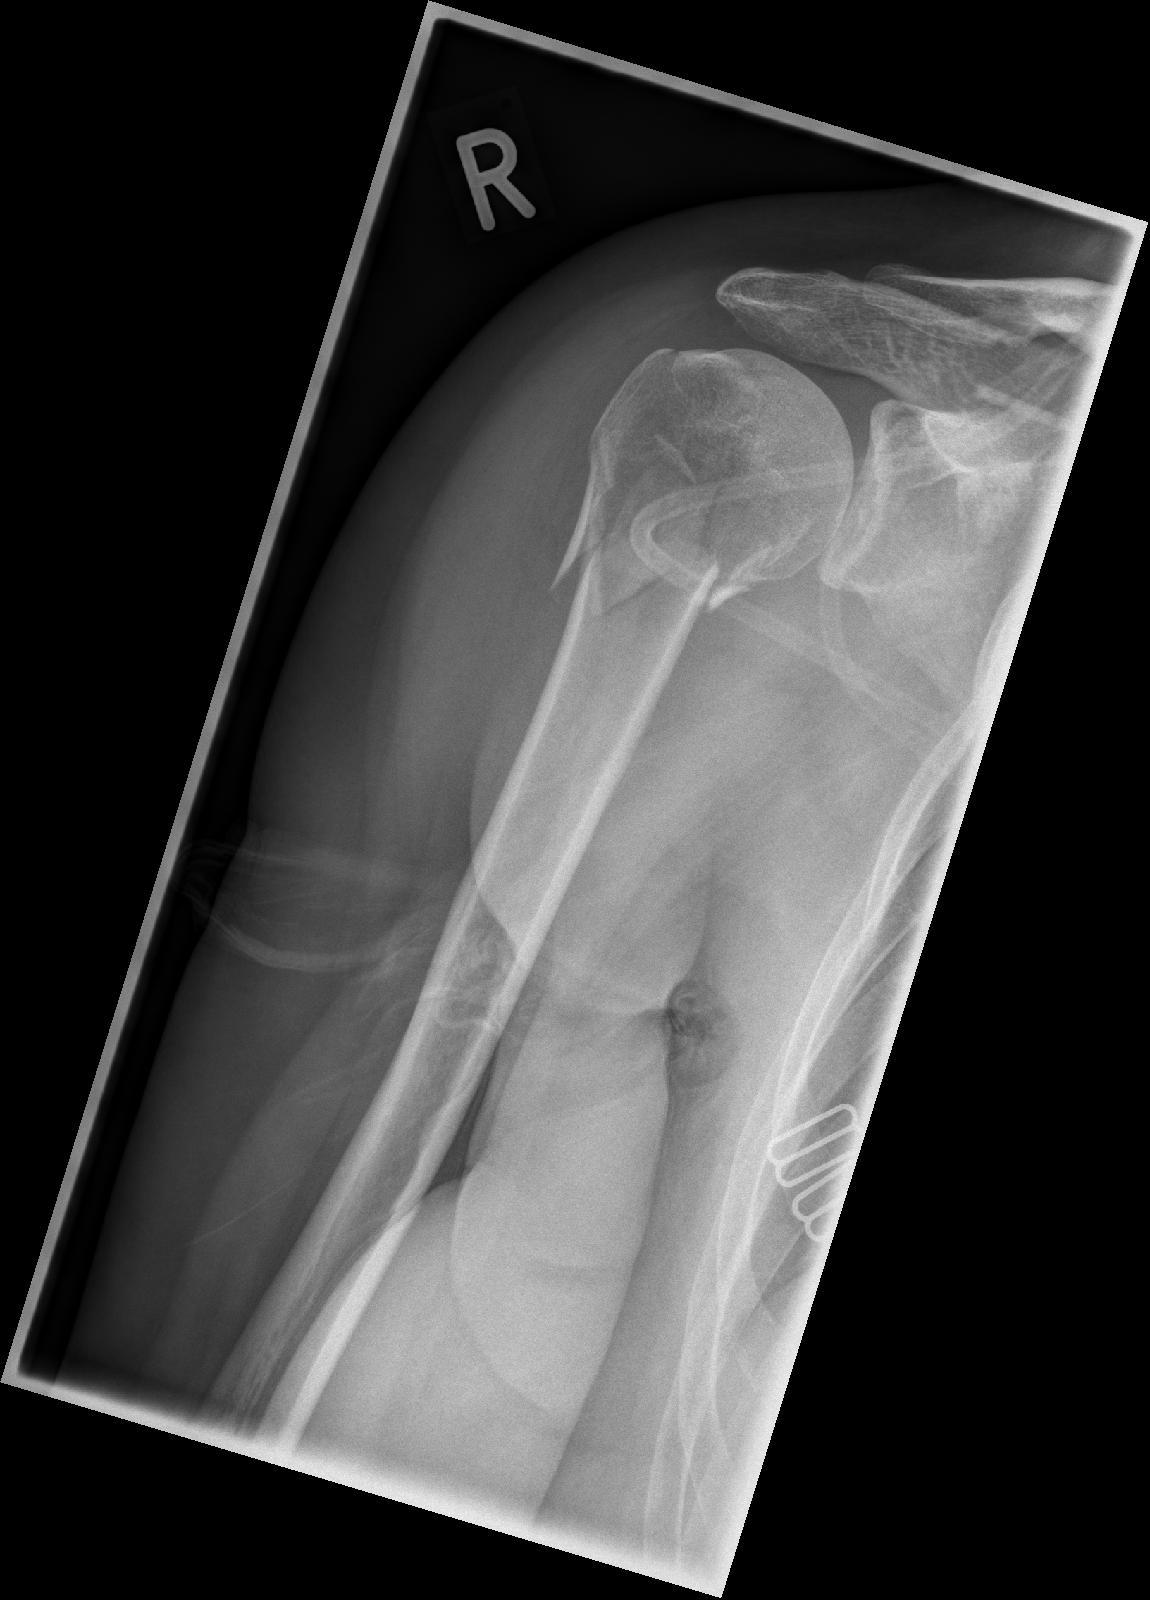

Hallo, der Knochen verknöchert gut und mir wurde in Aussicht gestellt, die Platte in 3 bis 6 Monaten schon zu entfernen. Die OP ist nun 7 Wochen her und ale sind mit dem Ergebnis zufrieden ausser ich.

Das Schulterblatt steht noch immer sehr raus, stört beim Sitzen. Das Schlafen ist mühsam, da ich eine Seitenschläferein bin und damit beim Schlaf die Schulter nach vorne fällt und wehtut.

Auch tagsüber ist die ganze Geschichte nicht so richtig schmerzfrei, so dass ich den Arm mal leinen Moment vergessen könnte. Es ist mehr die Rotorenmanschette, Schlüsselbeiregion, oberrer Rückenbereich über dem Schulterblatt was schmerzt ( Mischung aus Muskelkater, Verspannung). Ab und zu merke ich auch die Platte. Morgens ist das Gelenk steif und ich muss erstmal Aufwärmübungen machen. Ich komme über 90 Grad sowohl seitlich wie auch vorne, allerdings geht die Schulter mit hoch.

Wie lange muss ich noch mit Schmerzen rechnen, welche gezielten Übungen kann ich machen, um das Schulterblatt zu zentrieren, wie lange dauert der Muskelaufbau?

Hallo Anna,

das sieht tatsächlich schon ganz gut aus, wenn du mich fragst. Allerdings sieht man auch, dass die Schraubenköpfe einige mm aus dem Knochen hinaus ragen. Da kann ich mir gut vorstellen, dass du da schlecht drauf liegen kannst.

Was ich mir aber nicht vorstellen kann ist, dass das Schulterblatt-Problem damit zusammen hängt. Das Wegstehen des Schulterblattes ist meist eine muskuläre Störung, nämlich des "serratus anteriors" dieser wird wiederum vom "thoracicus longus" innerviert, das von den Halswirbeln C5-C7 entspringt. Das ganze nennt man "scapula alata"

Es gibt also eine Engstelle, dass den Nerv unter Druck setzt und somit den Muskel unterversorgt. Meistens wird diese Engstelle von einem Bandscheibenvorfall hervor gerufen! Aber auch von einer verschobenen 1. Rippe, dass den Nerven zwischen Schüsselbein und 1. Rippe einengt. Und genau das habe ich auf einem deiner Bilder entdeckt. Lass das mal checken!